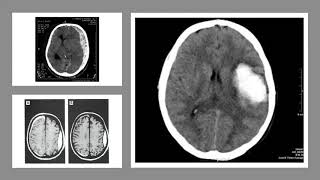

Для диагностики перелома таранной кости может потребоваться рентгенография или компьютерная томография стопы. Лечение может включать ношение гипса, бандажа или специальной обуви, а в некоторых случаях может потребоваться хирургическое вмешательство.